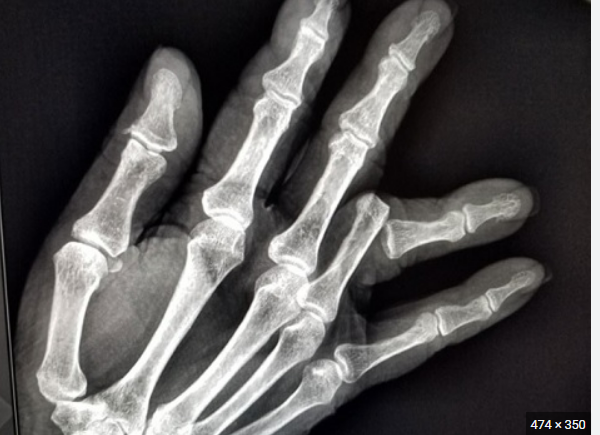

Trật khớp ngón tay